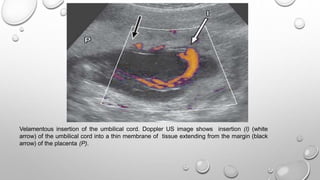

Velamentous insertion of the umbilical cord. Doppler US image shows insertion (I) (white

arrow) of the umbilical cord into a thin membrane of tissue extending from the margin (black

arrow) of the placenta (P).

 The umbilical cord typically inserts centrally, but eccentric and

velamentous (outside the placental margin) insertions also occur .

 Eccentric insertions are cord insertions that are less than 1 cm

from the placental edge. These are distinguished from a

velamentous insertion, where the umbilical cord inserts on the

chorioamniotic membranes rather than on the placental mass.

This membranous insertion results in a variable segment of the

umbilical vessels running between the amnion and the chorion,

unprotected by Wharton jelly